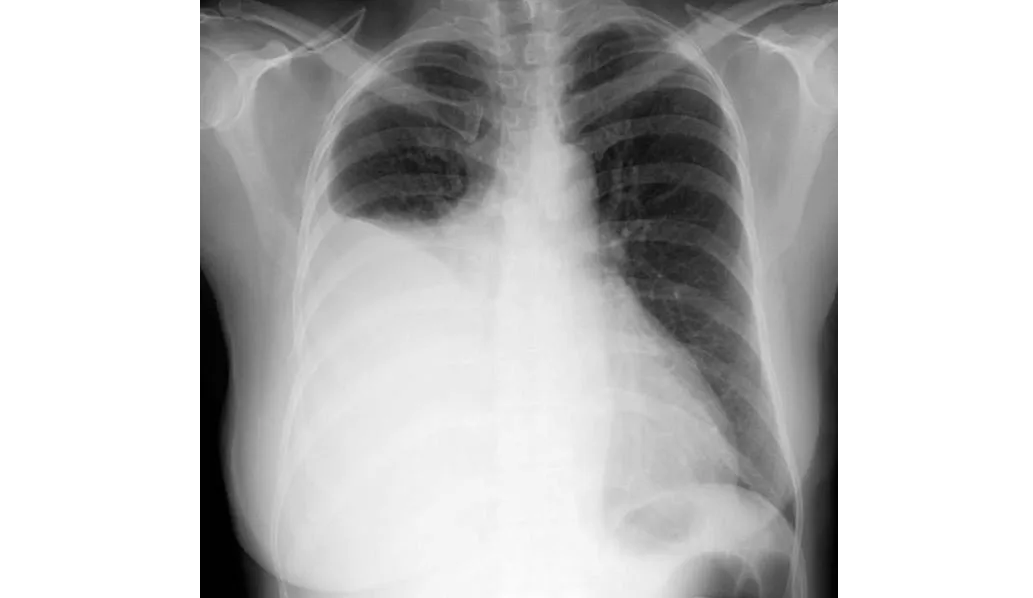

En este estudio sobre farmacocinética de antibióticos realizado en pacientes con derrames pleurales infectados se encontró que los antibióticos de uso común, como amoxicilina, metronidazol, piperacilina-tazobactam y clindamicina, alcanzan niveles en el líquido pleural equivalentes a los de la sangre y por encima de la CIM para las bacterias que se sabe que causan infección pleural. La preocupación sobre la penetración de antibióticos de uso común en el espacio pleural infectado (excepto por la trimetroprima) son infundadas. Thorax, 4 de julio de 2024.